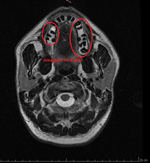

Ich habe auf Toxcenter endlich (aus dummen Zufall) die Bilder gefunden wo man Kieferaufnahmen erkennt, bewertet wurden, sowie auch Hirnaufnahmen.

https://web.archive.org/web/2014081...er.org/atlas-der-giftherde/index-bilder.php?0

Jetzt kann ich endlich versuchen mein OPG zu deuten. Ferner habe ich meinen Zahnarzt darum gebeten mir eine Überweisung zur Radiologie zu geben damit ich ein Vergleich des Kiefers vor und nach der Sanierung habe. Und auch um die aktuelle Belastung mit den Bildern und Dokumentationen von Toxcenter bewerten zu können. Oder es zumindest zu versuchen. Obs stimmt oder nicht wäre sowieso egal da sich an meiner Therapie nichts ändern wird. Das einzige wäre das sich Amalgamsplitter im Kiefer befinden. Die müssten dann operativ entfernt werden. In meinen Fall wären das 2 Zähne.